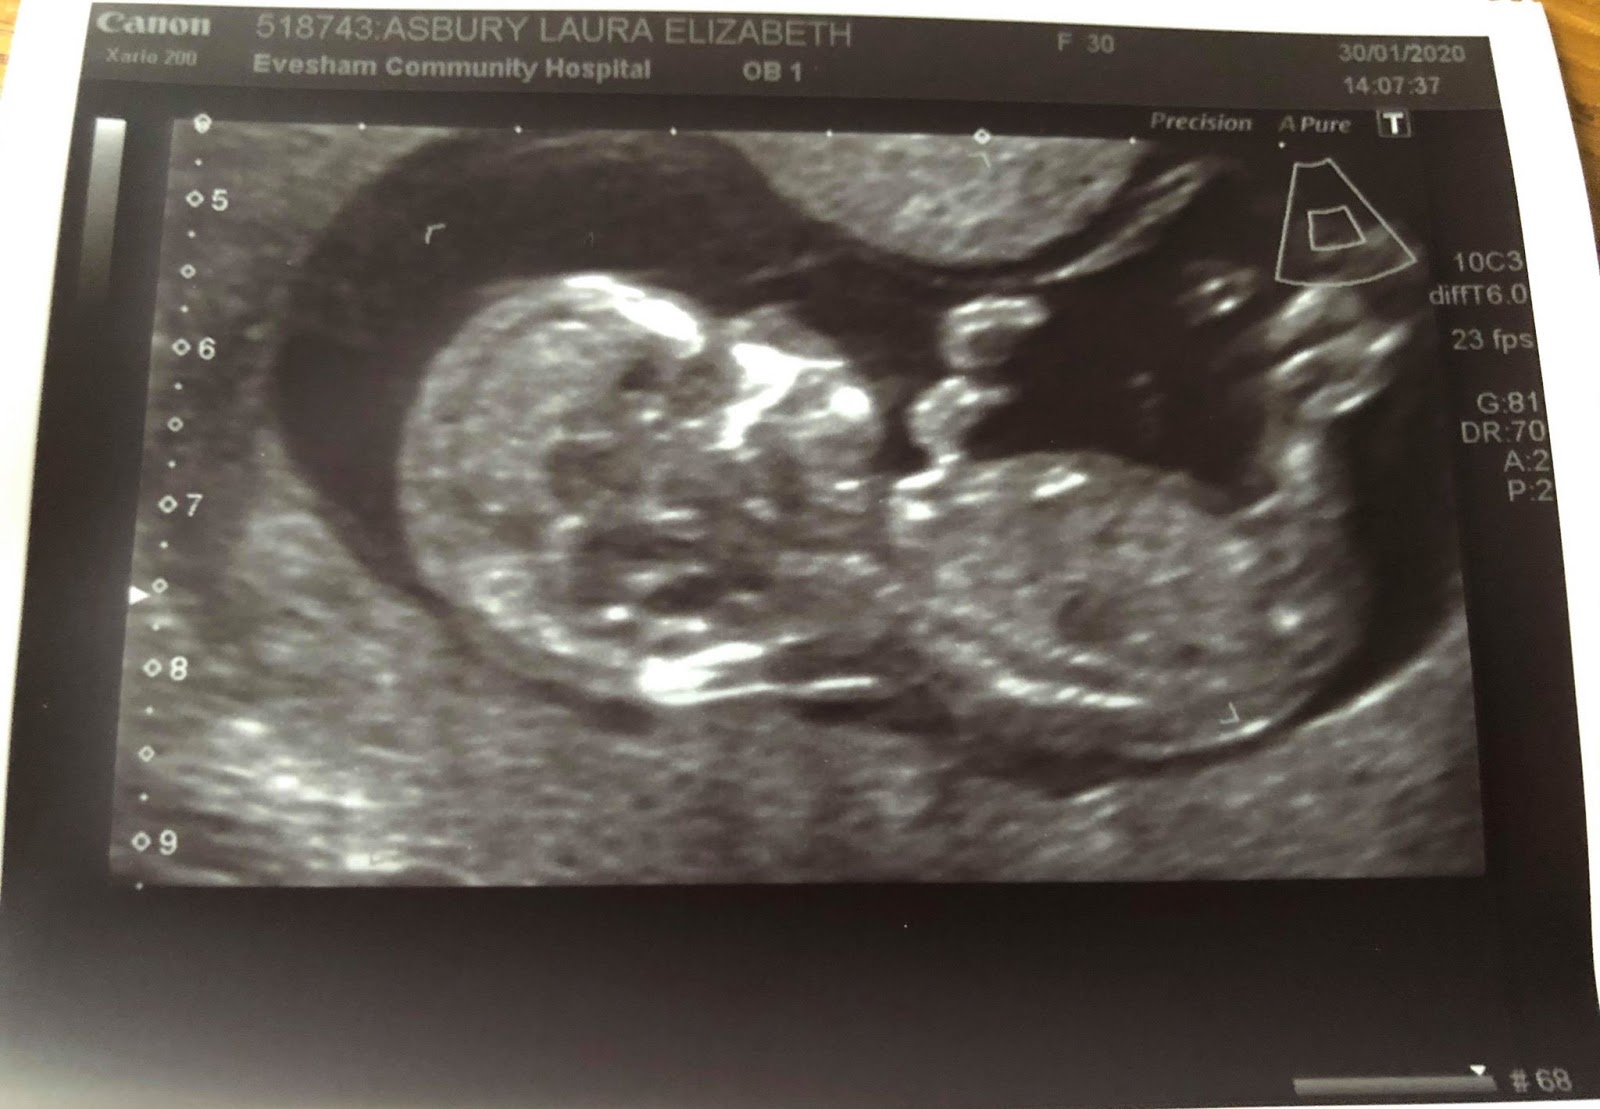

12 weeks . Between 8 - 12 weeks of pregnancy is a good time for a dating scan . A 2-D image of a baby at about 8-9 weeks . Small arms are becoming visible, sticking out slightly in the middle of the baby . The wavy line near the bottom of the image measures the heartbeat which in this baby is 188 beats per minute . It is normal to have a very fast heart rate at this gestation . Why might I need a scan before 12 weeks ?

A dating scan is an ultrasound scan carried out at around 12 weeks of pregnancy, that's used to work out your due date . It's likely to be the first time you see your baby and hear their heartbeat . This scan is also used to check that your baby's development is on track and is often part of combined screening for genetic variations, such as Down's syndrome , Edwards' Syndrome and Patau's Syndrome .